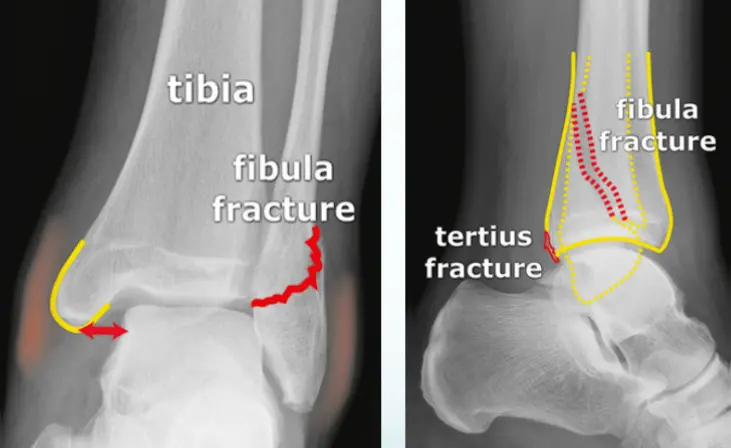

Patient: 32âyearâold male with a severe twisting ankle injury â painful, swollen and unable to stand.

Findings

- Site: lateral malleolus

- Fracture type: simple

- Fracture line: spiral

- Displacement: gap medially

- Special issue: possible ruptured deltoid ligament

- Site â Bimalleolar ankle fracture

- Type â C (fibular fracture above the syndesmosis); medial malleolus simple

- Fracture line â medial malleolus transverse; lower fibula complex (comminuted)

- Displacements â medial malleolus & talus shifted laterally

- Special issues â syndesmosis injured; intraâarticular fracture needs anatomical reduction (ORIF)

Site: Medial malleolus

Type: Simple intraâarticular fracture

Fracture line: Vertical

Displacements

- Gap in joint line

Special issues

- Requires anatomical reduction and absolute stability

- Possible lateral collateral ligament injury